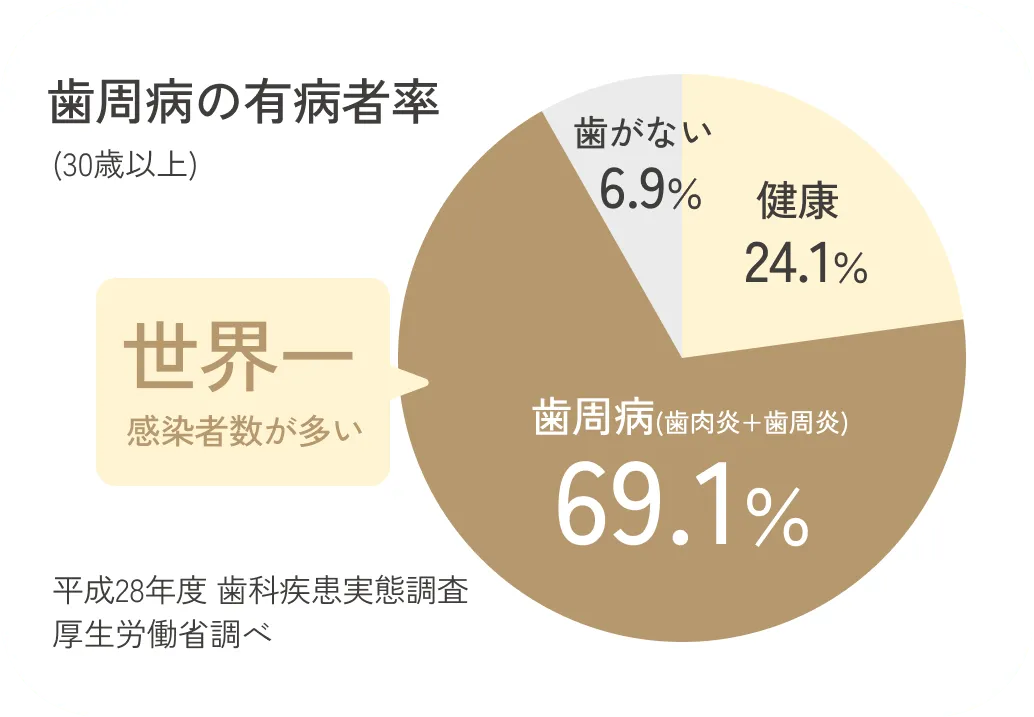

世界一患者数が多い病気

歯周病は、30代以上の10人に7人がかかっているとされており、ギネスブックにも「世界で最も蔓延している病気」として記録されたほど、だれもがなりうる病気です。中高年だけでなく若い世代も要注意。グラフは歯ぐきの炎症を含む軽度の症状も含めた発症率です。